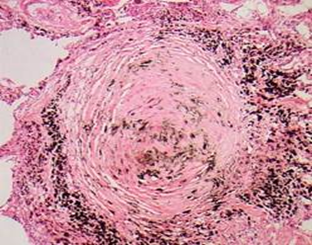

1.结节型矽肺:由于长期吸入游离二氧化硅含量较高的粉尘而引起的肺组织纤维化,典型病变为矽结节(silicoticnodule)。肉眼观,矽结节稍隆起于肺表面呈半球状,在肺切面多见于胸膜下和肺组织内,大小约为1~5mm。镜下观,可见不同发育阶段和类型的矽结节。早期矽结节胶原纤维细且排列疏松,间有大量尘细胞和成纤维细胞。结节越成熟,胶原纤维越粗大密集,细胞越少,终至胶原纤维发生透明性变,中心管腔受压,成为典型矽结节。典型矽结节横断面以葱头状,外周是多层紧密排列呈同心圆状的胶原纤维,中心或偏侧为一闭塞的小血管或小支气管。有的矽结节以缠绕成团的胶原纤维为核心,周围是呈漩涡状排列的尘细胞、尘粒及纤维性结缔组织。粉尘中游离二氧化硅含量越高,矽结节形成时间越长,结节越成熟,典型。有的矽结节直径虽很小,但很成熟,出现中心钙盐沉着,多见于长期吸入低浓度高游离二氧化硅含量粉尘进展缓慢的病例。淋巴结内也可见矽结节。

典型矽结节似“洋葱头”状结构 典型矽结节(“旋涡状”排列)